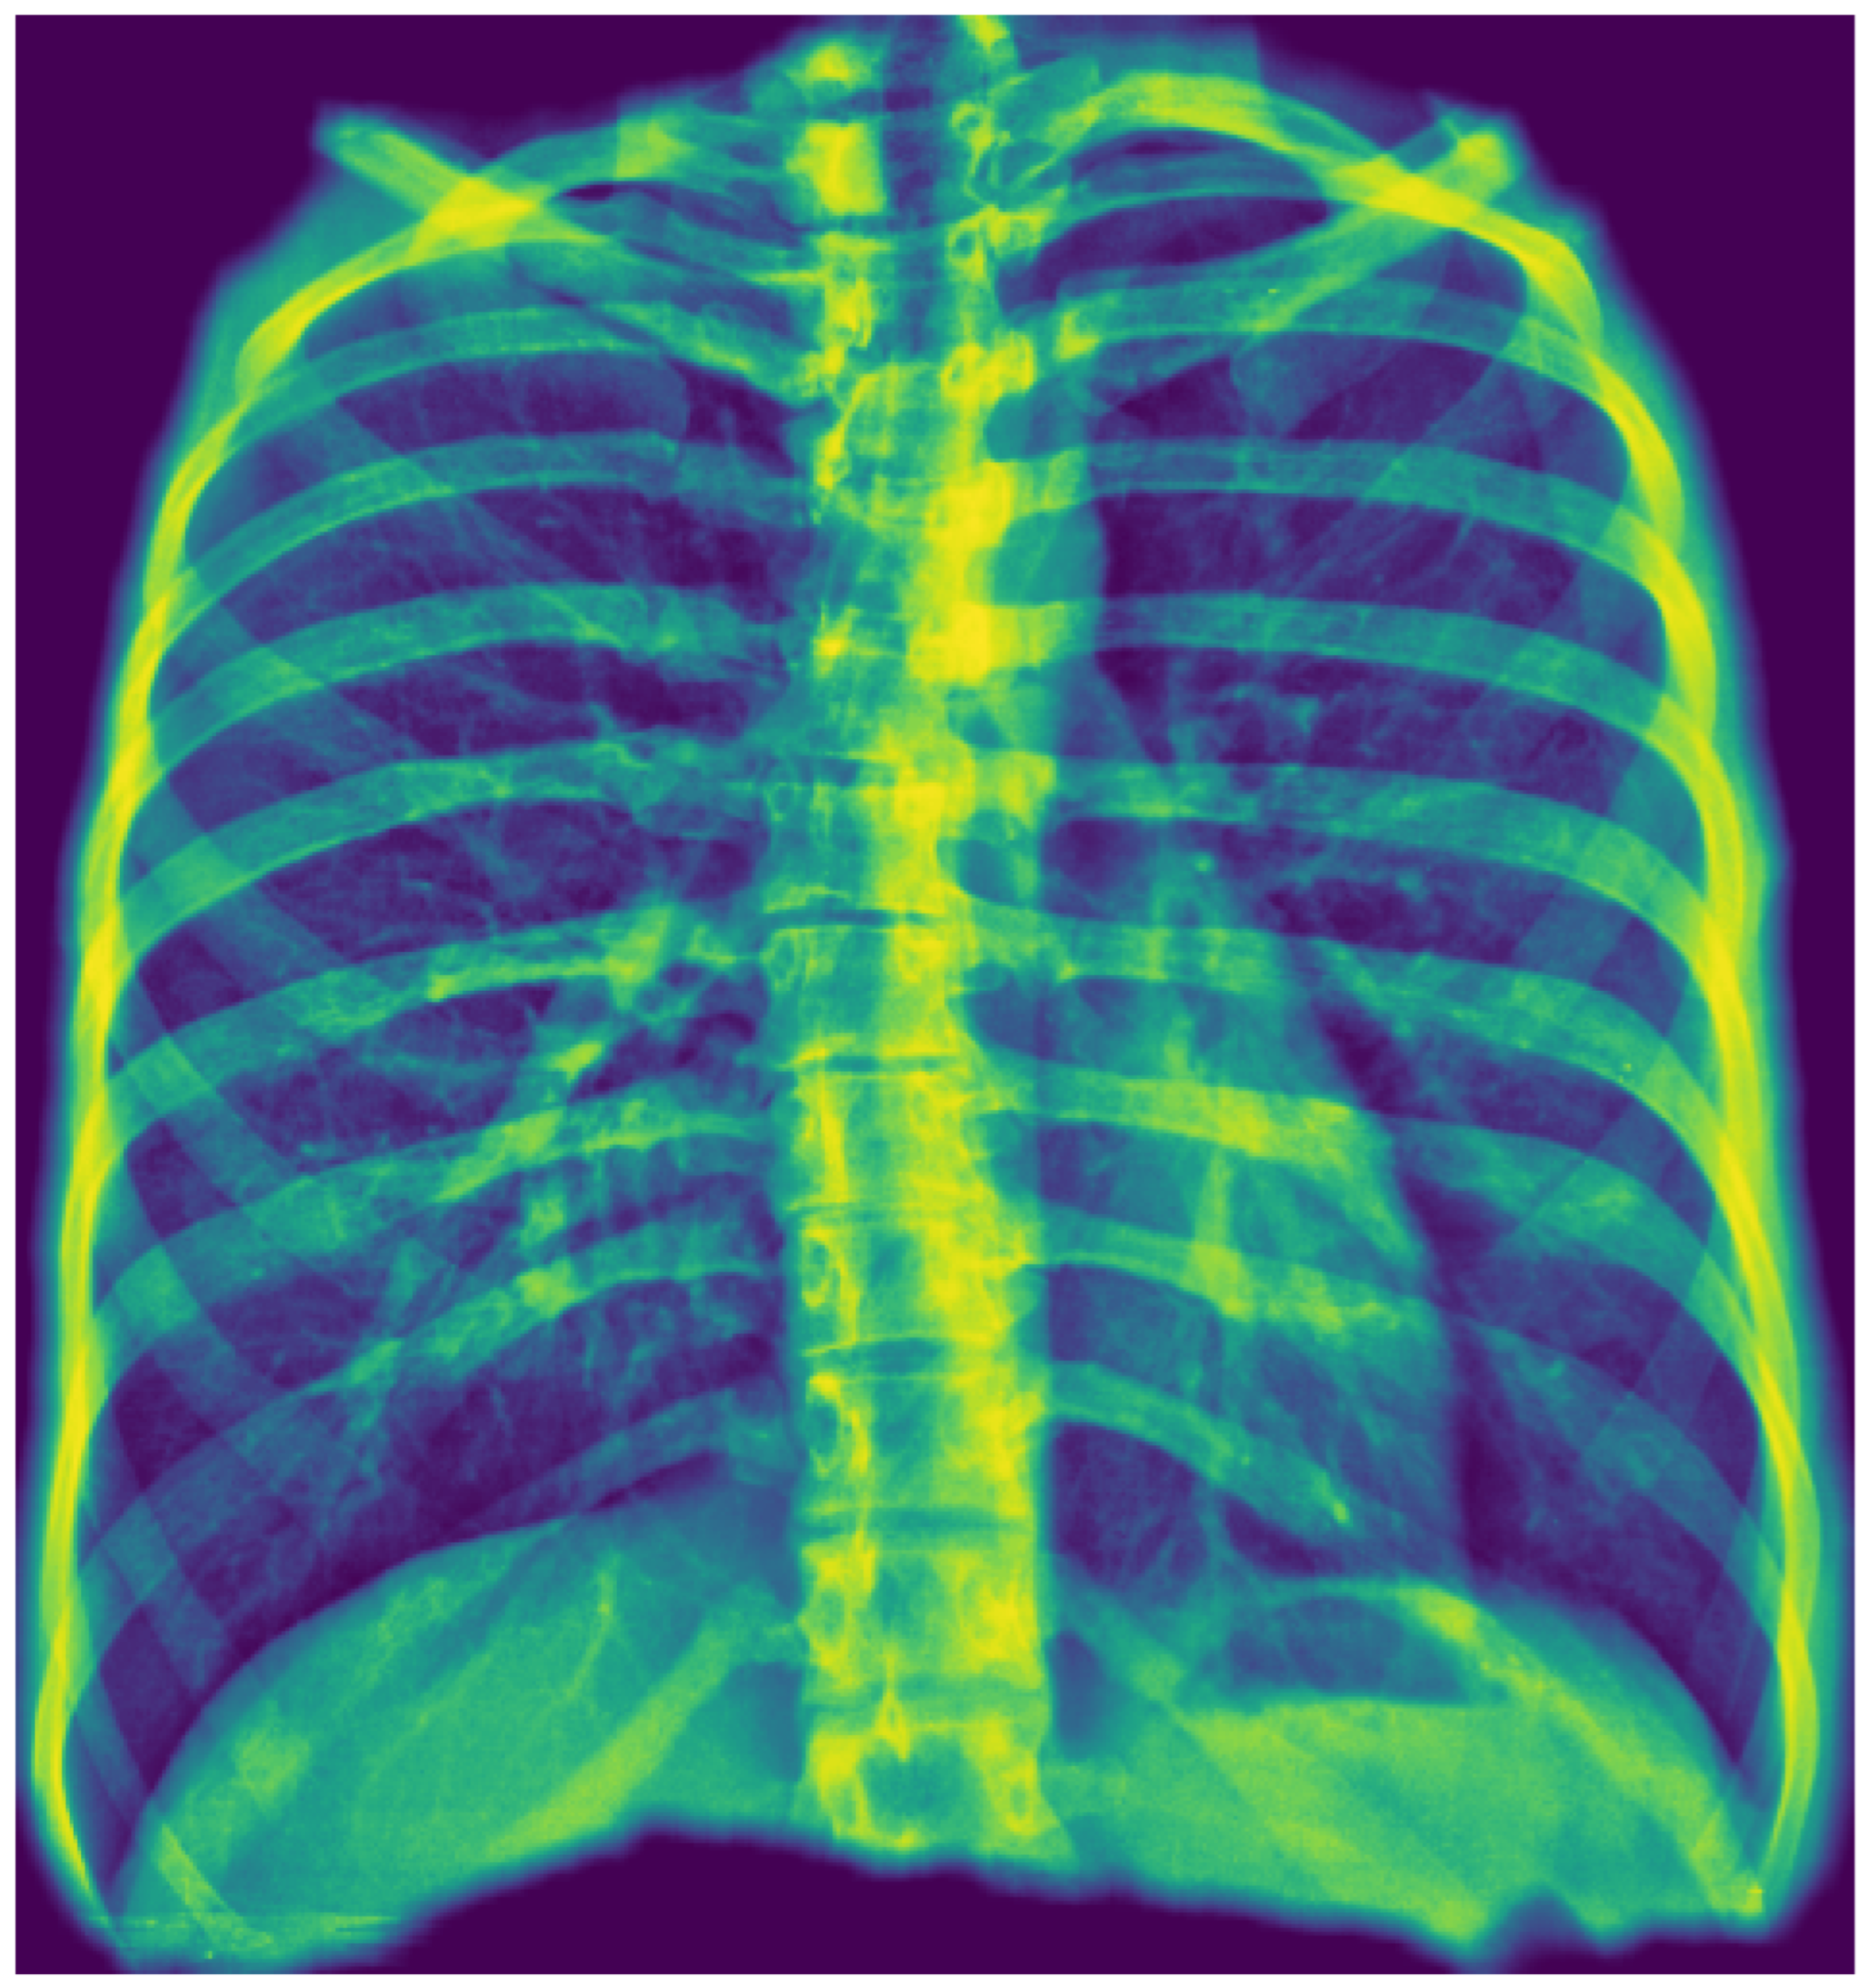

To enhance model transparency and validate spatial reasoning, we applied Gradient-weighted Class Activation Mapping (Grad-CAM) to visualize the regions most influential in classification decisions. Grad-CAM served a dual purpose in this context: first, it verified that the model’s predictions are based on clinically relevant regions within the segmented thoracic area; second, it contributed to interpretability by generating intuitive heatmaps that highlight the anatomical structures driving the model’s output. This step was crucial for improving classification accuracy and verifying that it relied on the correct visual cues, aligning with radiological expectations. For optimization, they were only generated when the classification probability score was above the defined threshold.

Representative Grad-CAM overlays are shown in Figure 3, Figure 4, Figure 5 and Figure 6, illustrating several different types of pathologies. These visualizations demonstrate where the algorithm focuses attention on the appropriate pathological regions, thereby reinforcing the validity and interpretability of the proposed pipeline.

Figure 11. A false negative example of a missed loculated pneumothorax. The presence of pulmonary markings (black arrow) beyond the pleural line (white arrowhead) may have misled the algorithm.